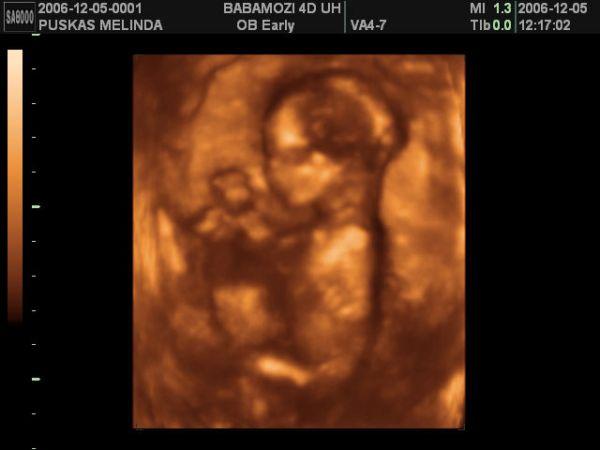

Mi ma voltunk terhesgondozason, megbeszeltuk a szulesi tervunket es nagyon elegedetten tavoztunk, mert abszolut hasonloan gondolkozunk a dokinkkal. Gyakorlatilag senkinek nem kell kompromisszumot kotni senkivel, az alapelveink megegyeznek. Mara meglett a Streptococcus B eredmenyem is, szerencsere ez is negativ, ugyhogy azt mondta, ha folyik a magzatvizem, nincs okom aggodalomra, nem kell rohanni a korhazba, csak mindent szep nyugodtan, ahogy megbeszeltuk. Azt mondta Levi gyakorlatilag kesz, most mar csak rajta mulik, mikor jon, es legyen minden kesz fogadasara. Es hogy ha addig nem, akkor jovo heten talizunk megint. Ettol iszonyu izgatott lettem, olyan jo volt ezt hallani, hogy most mar barmikor nyugodtan johet a baba! En nem tudom mindenki megorul az utolso honapban?!?!?!?